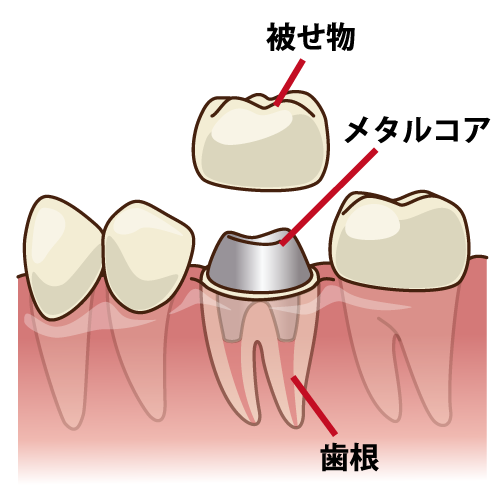

※メタルコアとは保険治療で最も一般的に使用されている金属の土台のことです。

通常、根の治療が終了すると、歯冠部を失ってしまった歯の根を補強するためにコアと呼ばれる土台を入れます。

クラウンのコアに使用される材料には、次のようなものがあります。

・メタル(銀合金)

・金合金

・ファイバー(グラスファイバーとコンポジットレジン)

メタルコアは強度があること、保険が適応されるなことなどから多く使用されていますが、デメットが多々ありますので注意が必要です。

ファイバーコアは、保険が適応されないというデメリットはありますが、歯と同じくらいの硬さであること、柔軟性があることから、歯の破折を招きにくい、変色が起こらない、歯ぐきが黒ずまない、金属アレルギーを起こさない、切削量が少ないというメリットがあります。失った歯質は取り戻せないため、慎重な選択が重要です。